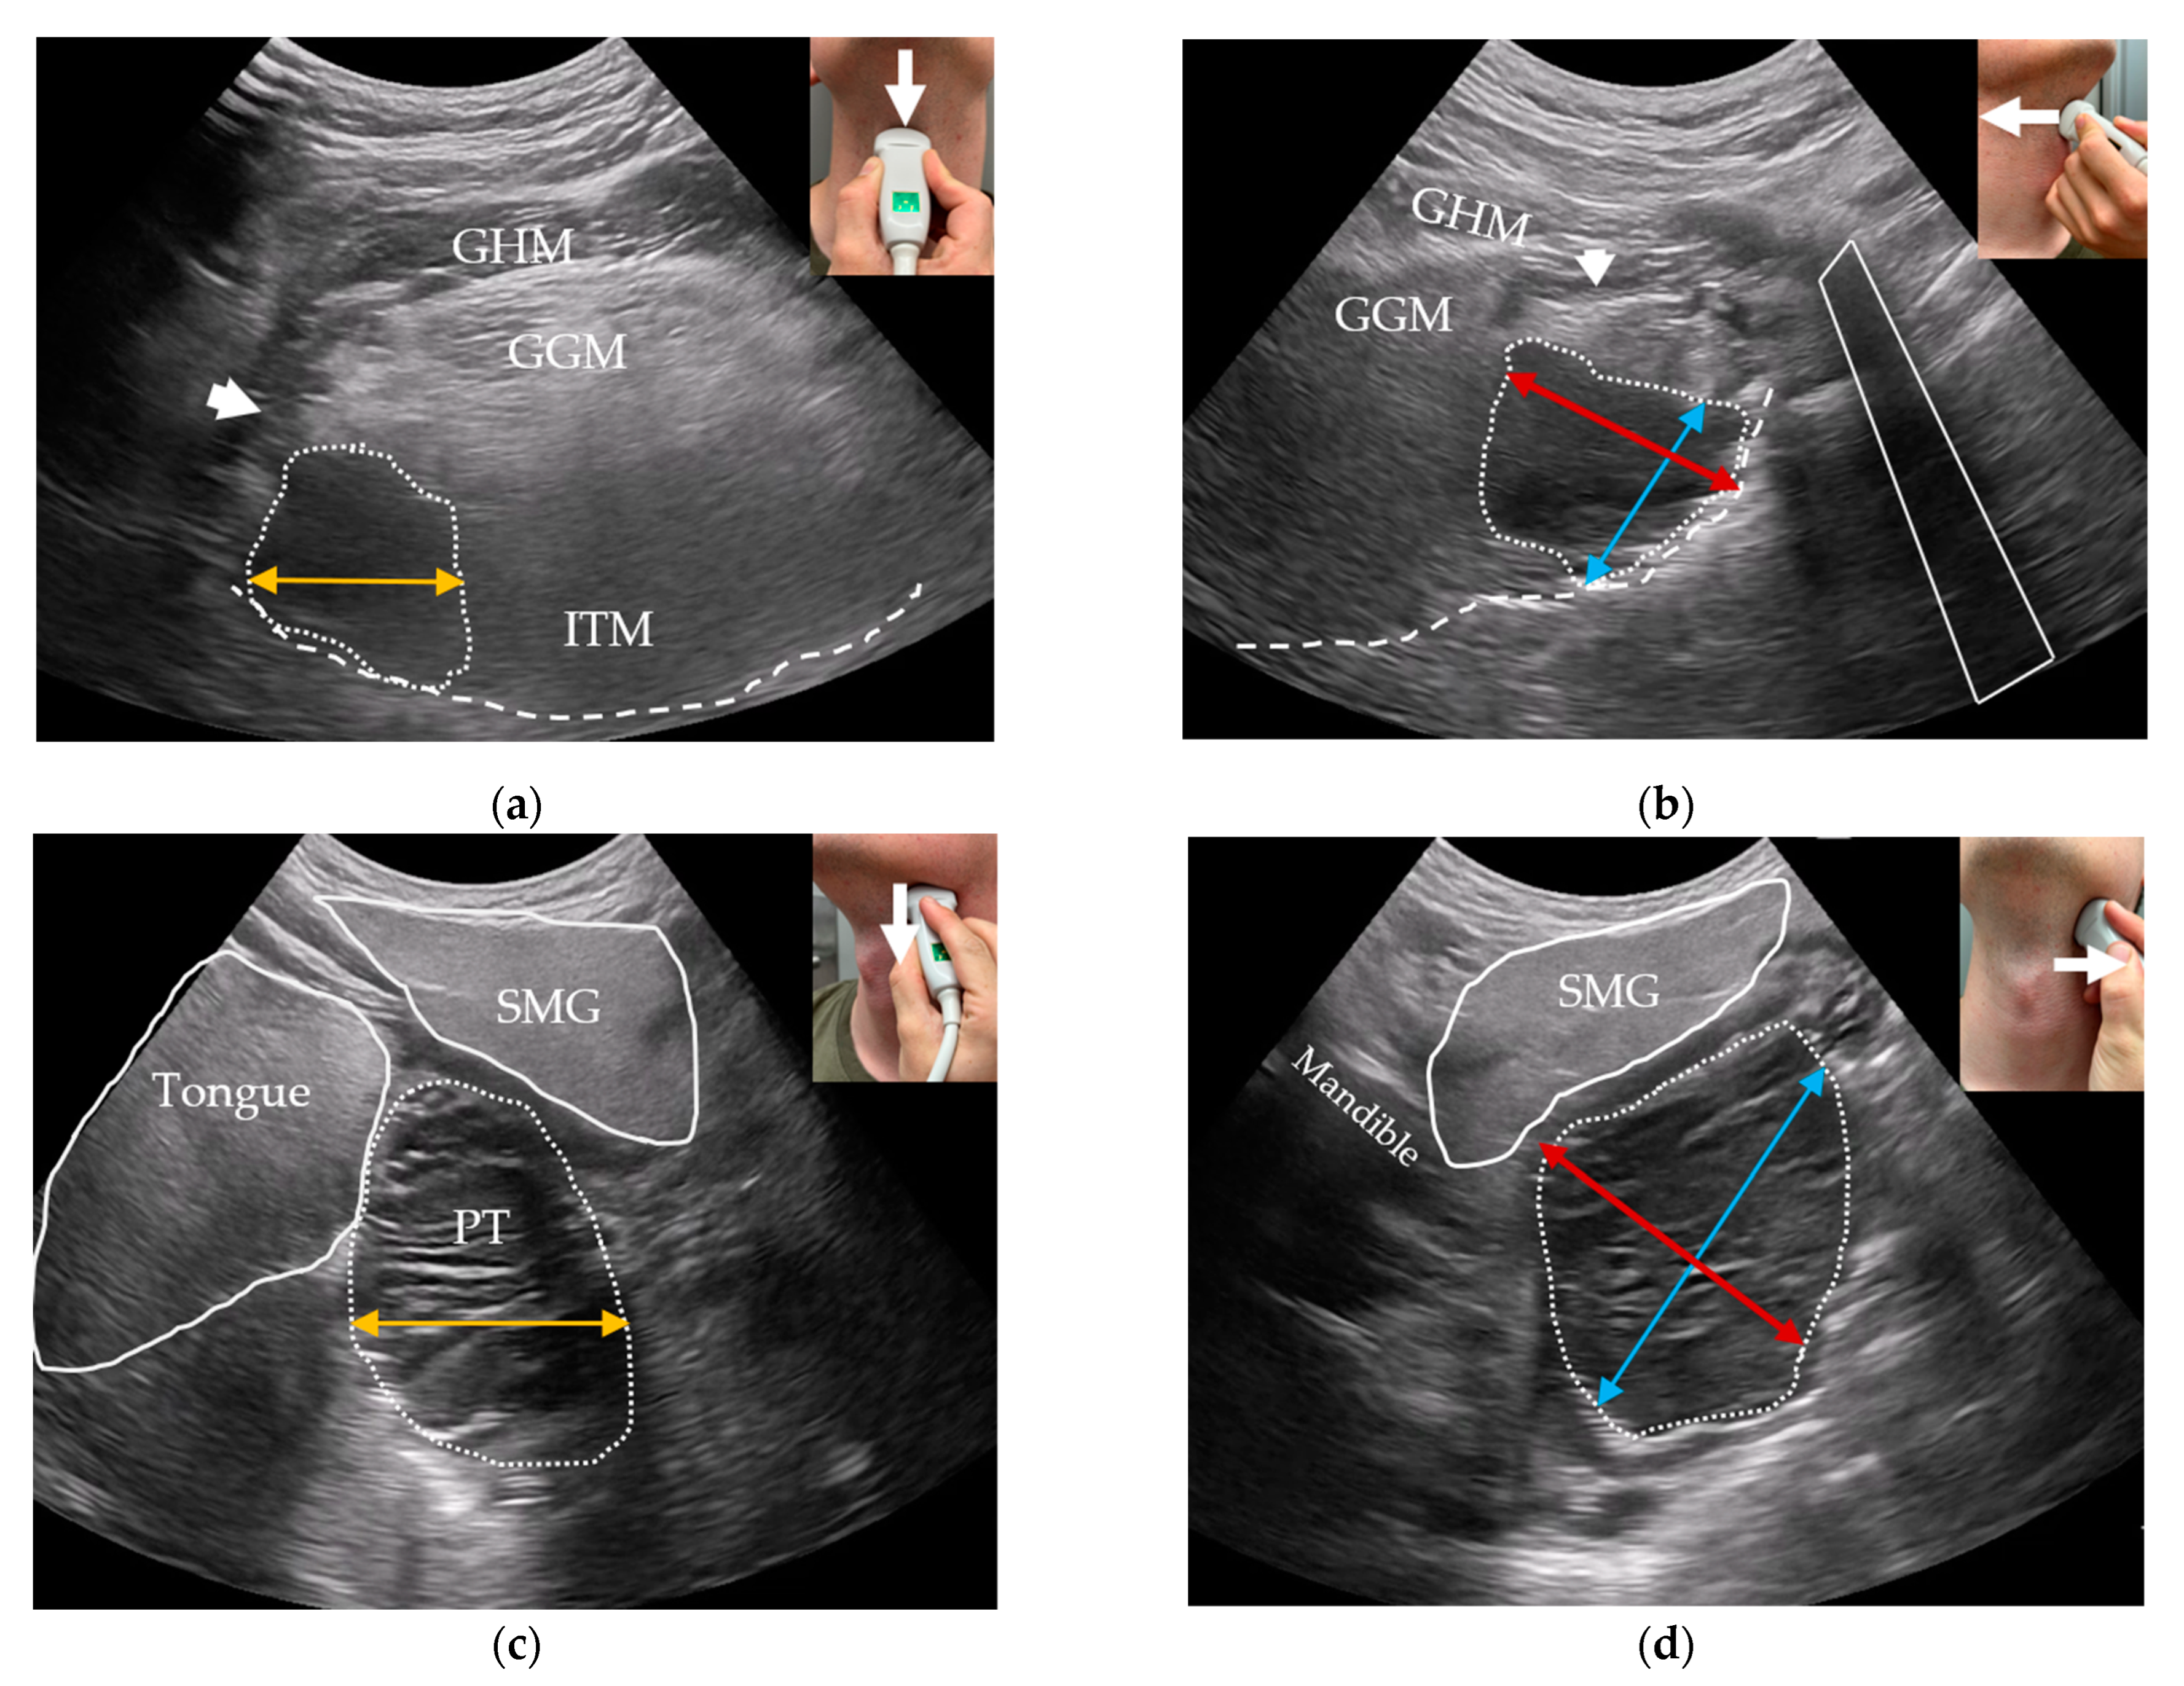

Following clinical examination, included patients will be offered combined transoral and transcervical US of the oropharynx during the initial work-up as an extension of the clinical work-up. This will be performed prior to any available T-site histopathology results. US will be performed blinded to any cross-sectional imaging. To perform the transoral US, a patient seated upright in an examination chair will receive topical anesthetic spray applied to both palatine tonsils and the posterior portion of the tongue using xylocaine (10 mg/dose). Patients are informed that eating or drinking following local anesthesia should be postponed for up to one hour due to the risk of aspiration. Patients are instructed to swallow the anesthesia. A sheathed or disinfected “hockey-stick” or small-footprint US transducer is advanced into the patient’s mouth and placed on top of the suspected palatine tonsil in the transverse plane (Figure 1a,c) with a gentle swiping motion from the cranial to caudal pole. The transducer is rotated to the sagittal plane by positioning the tip of the transducer caudally (Figure 1b,d) and a swipe is performed from the lateral to the medial edge. The procedure is repeated contralaterally. Power Doppler is performed on both palatine tonsils. If a lingual tonsil tumor is suspected, a transoral US is attempted (Figure 2).

Figure 1. Transoral US of the palatine tonsils: (a) a sheathed US transducer placed on the right palatine tonsil (arrow: swipe direction cranial-to-caudal) in the transverse plane; (b) sagittal plane (arrow: swipe direction lateral-to-medial); (c) transverse US image with Power Doppler of a right palatine tonsil tumor (dotted outline) with underlying constrictor muscle (dashed line), internal carotid artery (ICA), stylopharyngeus muscle (SPM), styloglossus muscle (SGM), and medial pterygoid muscle (MPM). The anteroposterior (red bi-directional arrow) and mediolateral (orange bi-directional arrow) tumor diameters are shown; (d) sagittal US image of the same tumor (dotted outline) with the underlying constrictor (dashed line), ICA, and MPM. In sagittal view, the MPM can be used as a craniolateral landmark. The craniocaudal diameter of the tonsil is shown using a blue bi-directional arrow.

For transcervical US, the tongue and lingual tonsils are visualized using a curved low-frequency transducer placed on the suprahyoid region in a transverse plane. A swipe from the chin to towards the hyoid bone is performed (Figure 3a). The probe is then rotated 90 degrees clockwise to the sagittal plane and two consecutive midline-to-lateral swipes are performed for each side of the base of tongue (Figure 3b). Similarly, the palatine tonsils are visualized in two planes in the submandibular gland region (Figure 3c,d) [20]. The quality of both transoral and transcervical US scans will be rated using a 5-point Likert scale (1—Very poor; 2—Poor; 3—Fair; 4—Good; 5—Excellent) [35]. Patient-reported discomfort from transoral US will be quantified using an 11-point numeric rating scale from 0 (no discomfort) to 10 (worst discomfort imaginable).

Figure 3. Transcervical US of the palatine and lingual tonsils. Transducer orientations are represented on the top right of each image with a white arrow representing the swiping directions: (a) oblique transverse US image of the base of tongue with the geniohyoid (GHM), genioglossus muscles (GGMs), intrinsic tongue muscles (ITMs), hyoglossus muscle (arrowhead), oral surface of the tongue (dashed line), and a hypoechoic endophytic tumor in the right base of tongue (dotted outline). The mediolateral diameter of the tumor is shown (orange bi-directional arrow); (b) sagittal US image of the same tumor with the hyoid bone’s acoustic shadow shown (white outline)—craniocaudal (blue bi-directional arrow) and anteroposterior (red bi-directional arrow) tumor diameters; (c) Oblique transverse US image of a benign hyperplastic palatine tonsil (PT, dotted outline), the submandibular gland (SMG), tongue, and mediolateral diameter of the PT (orange bi-directional arrow); (d) sagittal US image of the same PT with the mandible’s acoustic shadow shown anteriorly as a landmark for the anteroposterior diameter (red bi-directional arrow). The craniocaudal diameter (blue bi-directional arrow) of the PT is parallel to the hyperechoic mucosal surface seen below the tonsil.

All US tumor measurements will be registered blinded to MRI and PET/CT. Small tumors will be measured transorally if they fit within the field-of-view of the transoral US transducers. In transverse transoral US of the palatine tonsils, the medial pterygoid muscle will serve as a lateral landmark (Figure 1c): the mediolateral diameter will be measured from the medial pterygoid muscle towards the tonsil’s medial surface. A perpendicular measurement will be performed for the anteroposterior diameter (Figure 1c). In sagittal view, the length of the tonsil tumor from the upper to lower pole will be measured as the craniocaudal diameter (Figure 1d). For the lingual tonsil, the hyoid bone will serve as a caudal landmark for the craniocaudal tumor diameter (Figure 2b). A perpendicular anteroposterior diameter will be measured through the tumor from the posterior surface of the lingual tonsil in the direction of the tongue apex. The mediolateral diameter is more difficult to measure transorally due to technical limitations of the US transducers. Instead, this diameter will be measured transcervically if the tumor can be visualized.

The greatest tumor diameters in three dimensions and an ultrasonographic T-stage will be registered considering tumor invasion of deep structures according to the UICC8 staging system. Transcervical US will be used to measure primary oropharyngeal tumors that are larger than the transoral US transducer’s field-of-view (Figure 3). We will register whether the transoral US or transcervical US was superior in terms of tumor measurement and invasion.